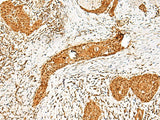

PPOX Polyclonal Antibody Reactivity Human

Applications IHC

IHC 1:50-1:300